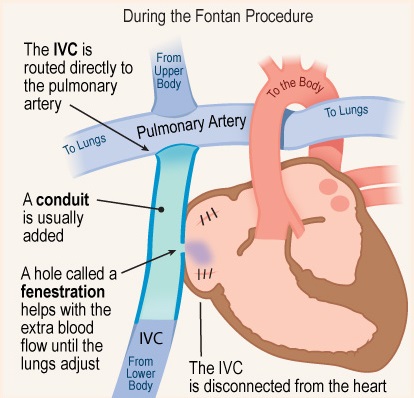

Overview

Package includes:

Days in hospital : 12 to 13 Days (For patient and one attendant)

Days in hotel : 16 Days (For patient and one attendant)

Room type in hospital : Shared

Room type in hotel : Private

Hotel category: Standard

Value added benefits of the Fontan Procedure:

Ø Doctor consultation charges

Ø Lab tests and diagnostic charges

Ø Room charges inside hospital during the procedure

Ø Surgeon Fee

Ø Nursing charges

Ø Hospital surgery suite charges

Ø Anesthesia charges

Ø Routine medicines and routine consumables (bandages, dressings etc.)

Ø Food and Beverages inside hospital stay for patient and one attendant.

Extra benefits: